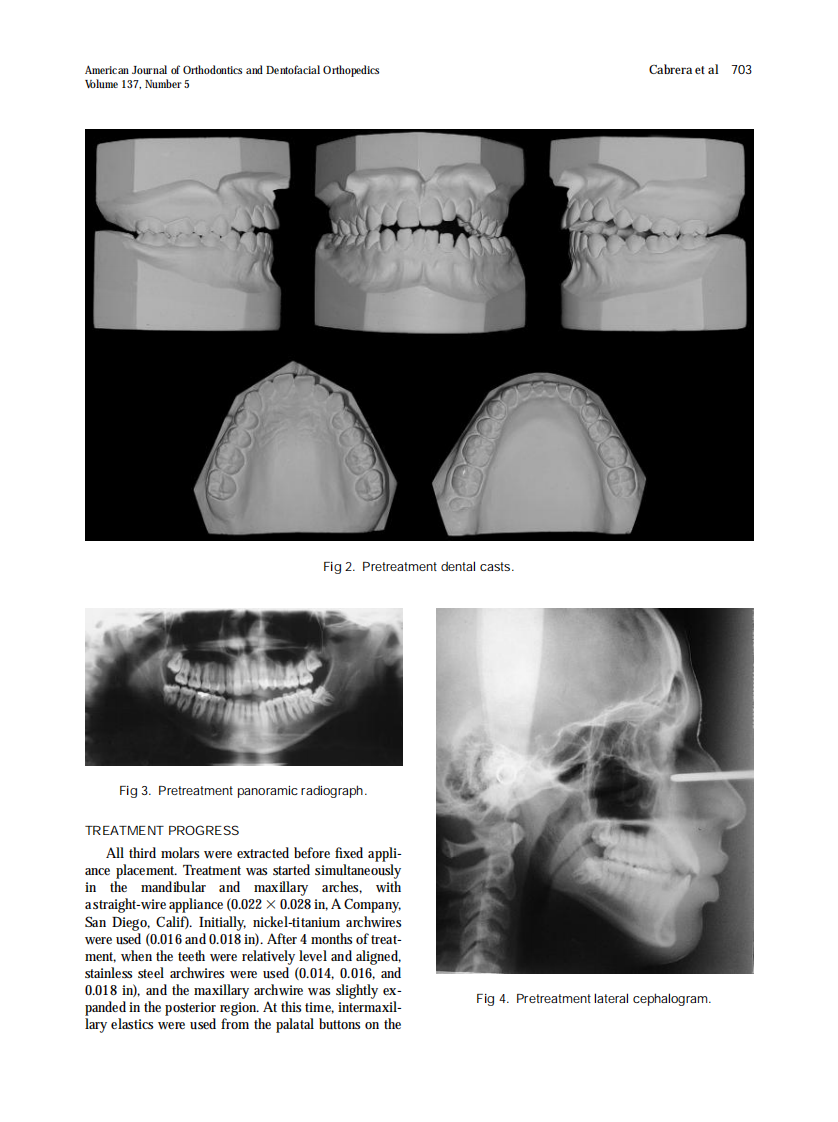

AJO-DO

2010_137_5_701_711.pdf